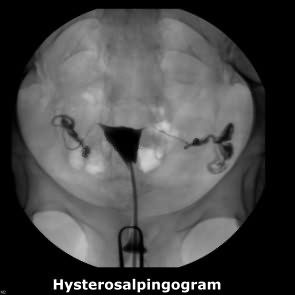

博元送子 ​專車: 她輸卵管不通,經過腹腔鏡 和剖腹術仍無法挽救也不孕症2年,博元婦產科試管嬰兒成功, 她順利的在40週以自然產方式生下寶寶,體重3550公克 ​王小姐,她因為輸卵管不通,在一家醫院做過腹腔鏡也做過剖腹都無法矯...

她輸卵管阻塞,做了3次試管嬰兒都失敗,轉到博元婦產科,先以腹腔鏡手術,再做試管嬰兒,竟3胞胎 不孕症: 雙邊輸卵管阻塞 不孕症有2年 曾經做過試管嬰兒3次通通失敗 ​陳小姐她已經不孕症2年,因為輸卵管阻塞積水曾經在一家醫院做過腹 腔鏡...